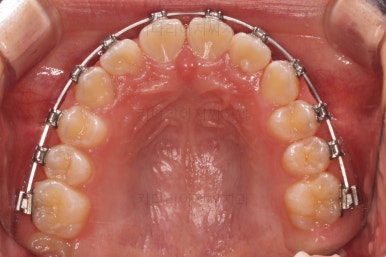

초진 시 입안의 모습입니다.

앞니가 안으로 굽어 들어간 양상인데요. 흔히 "옥니"라고 표현합니다.(뻐드렁니의 반대개념)

전반적으로 치열이 삐뚤삐뚤하고요.

오른쪽 상단 사진을 보시면 어금니의 높이와 앞니의 높이의 차이가 많이 나요.

앞니가 솟구쳐 있는 양상인데요.

그 이유 때문에 어금니로 다물었을 때 위아래 앞니가 많이 겹쳐서 아래 앞니가 아예 보이지 않는 상황이었어요.

이를 "과개교합"이라고 표현합니다.

그리고 전반적으로 아래 치열이 윗니에 비해 뒤로 밀려 있어서, 어금니의 맞물림이 좋지 못하고 듬성듬성해 보이는 상황이었어요.